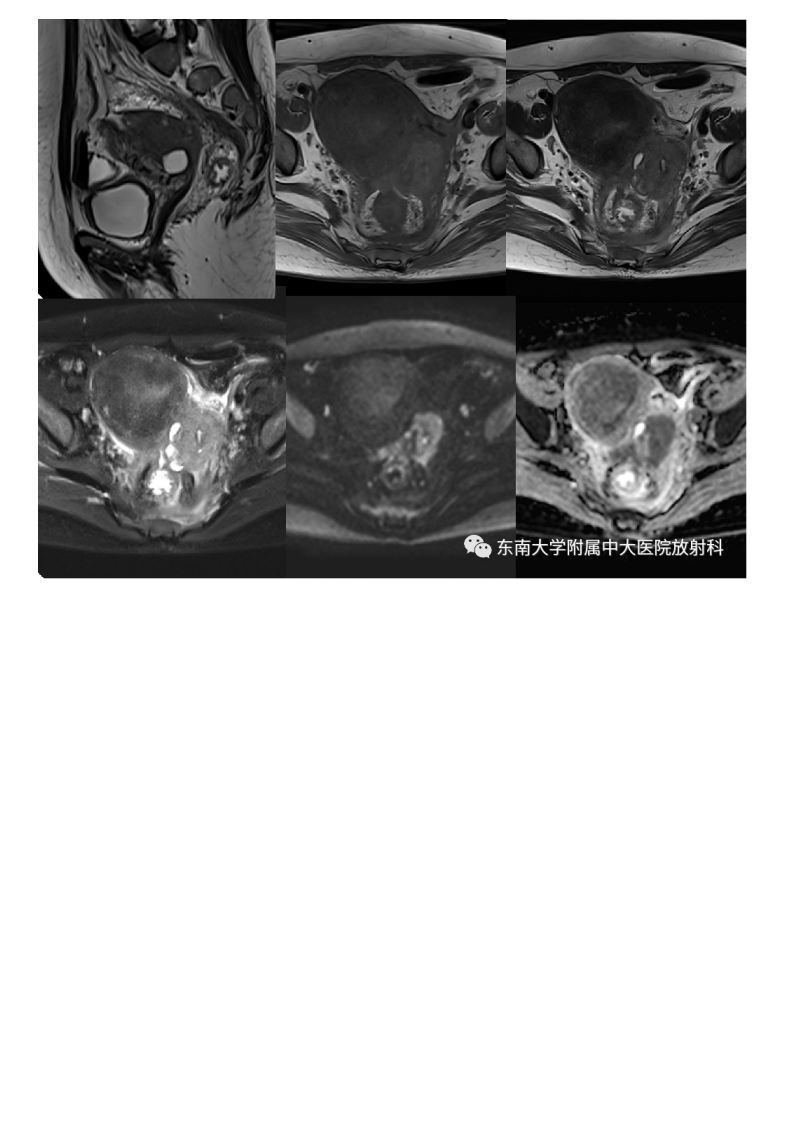

20210525_2【晨读结果公布】2021.05.24生殖系统疾病——病例1病理倾向于炎性假瘤;病例2:子宫内膜样癌;病例3:宫颈富细胞性肌瘤.pdf